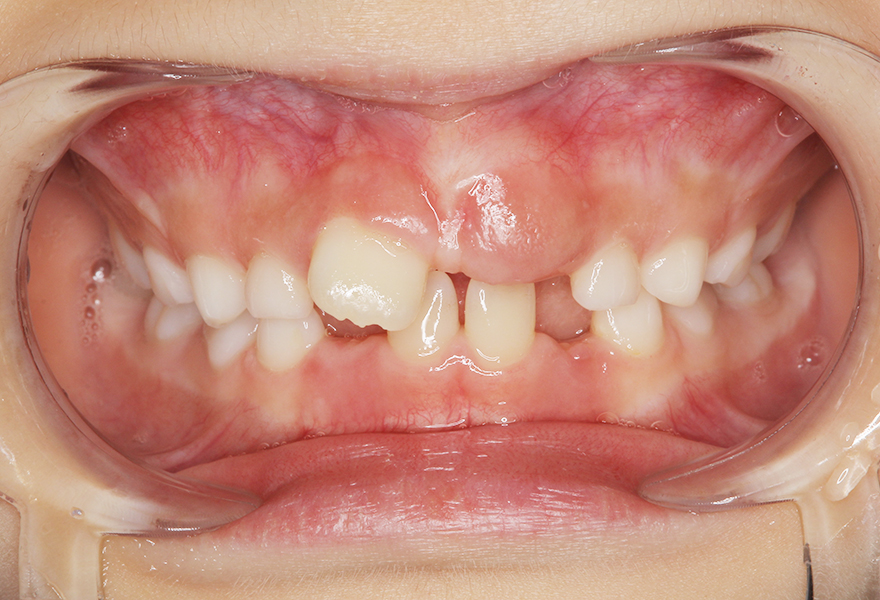

小児矯正(MRC)により歯列と咬合を改善した症例(8歳女児)

治療前 ![]() |

前歯のガタつきと噛み合わせのズレが気になるとのことで来院されました。上下の前歯が重なり合い、将来的な永久歯の生え変わりや歯並びへの影響を心配されていました。 |

拝見したところ、上下顎前歯部に叢生傾向があり、歯列の幅が狭く、舌の位置や口呼吸などの口腔習癖も歯並びに影響している状態でした。このまま成長すると、将来的に本格的な矯正治療が必要になる可能性が高いと判断しました。 |